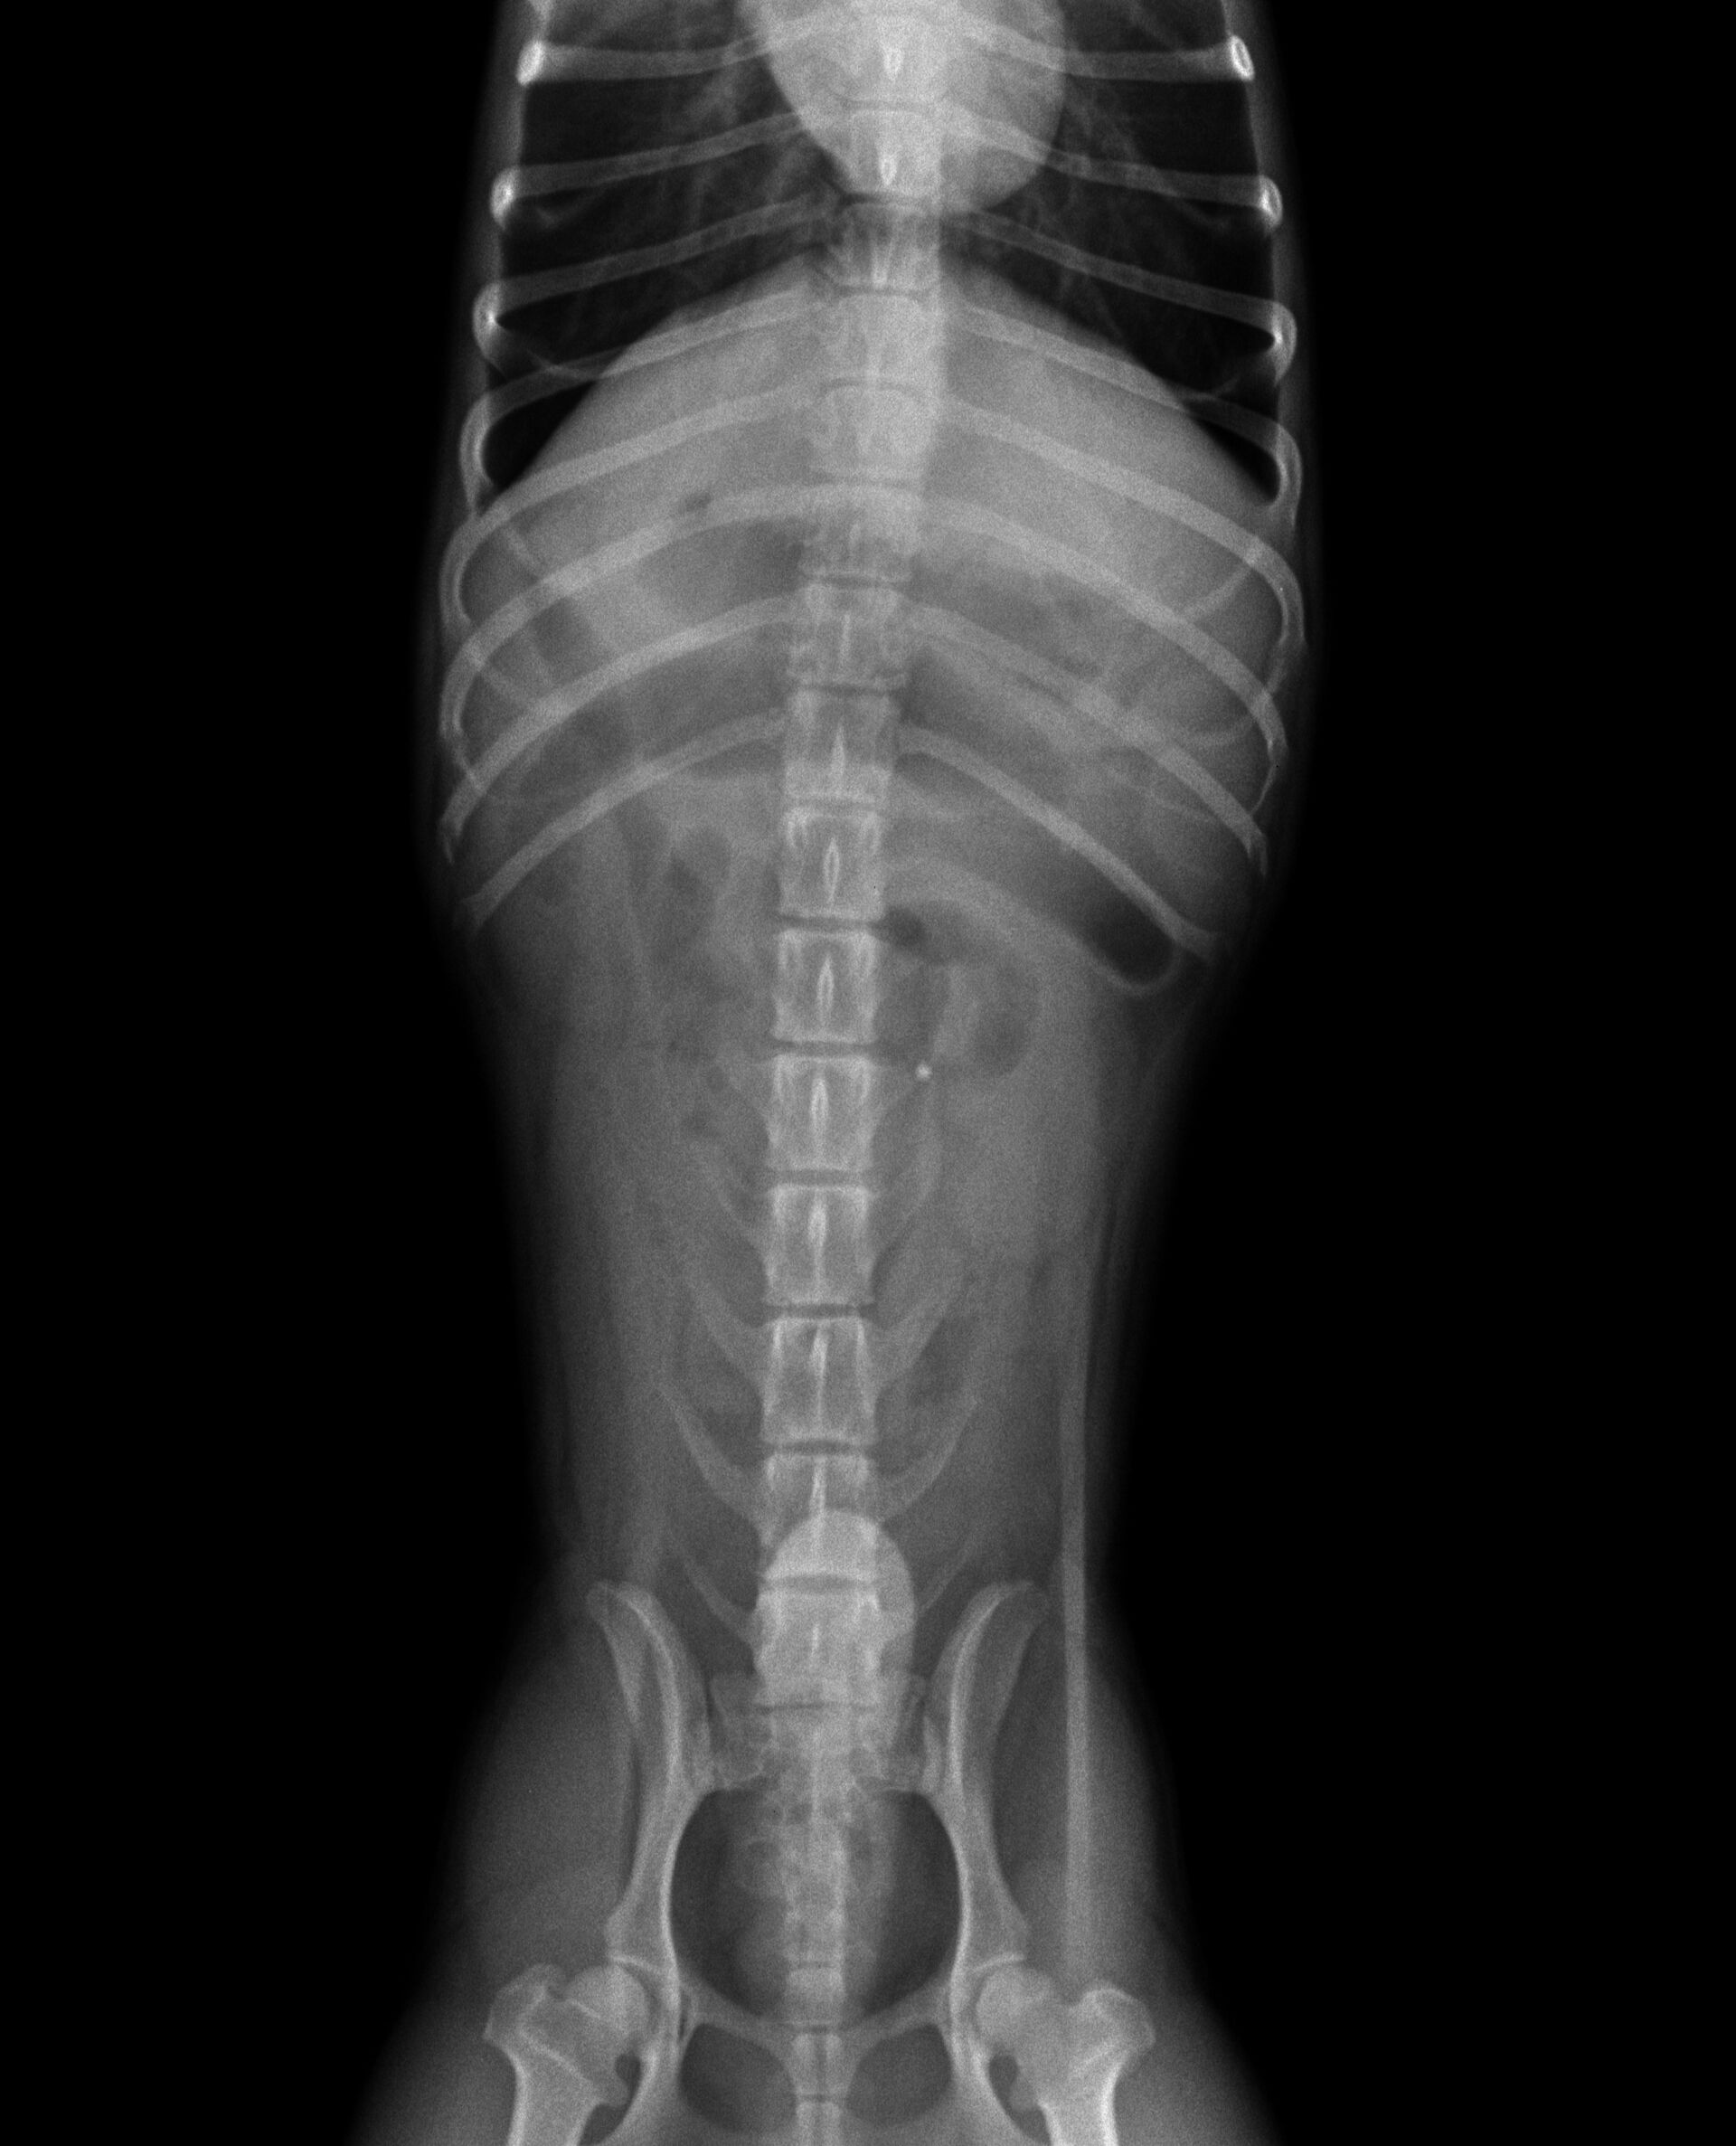

今年もあと1日となってしまいました。久々の投稿になってしまいましたが、今年最後の症例報告をさせていただきます。症例は1歳のジャックラッセルです。飼い主さんによると、日頃はすごく元気で食欲も旺盛なワンちゃんが突然何回も嘔吐し、食欲・元気がまったくなくなったとのことでした。元気で若いワンちゃんが突然、食欲廃絶、元気消失となると、一番疑われるのは異物の誤嚥です。そこで、すぐにレントゲンを撮りました。それが下の写真です。

胃から十二指腸にかけて普通より少しガスが多く認められました。益々異物による腸閉塞が疑われたので、バリウム検査を行うことにしました。その結果が以下です。